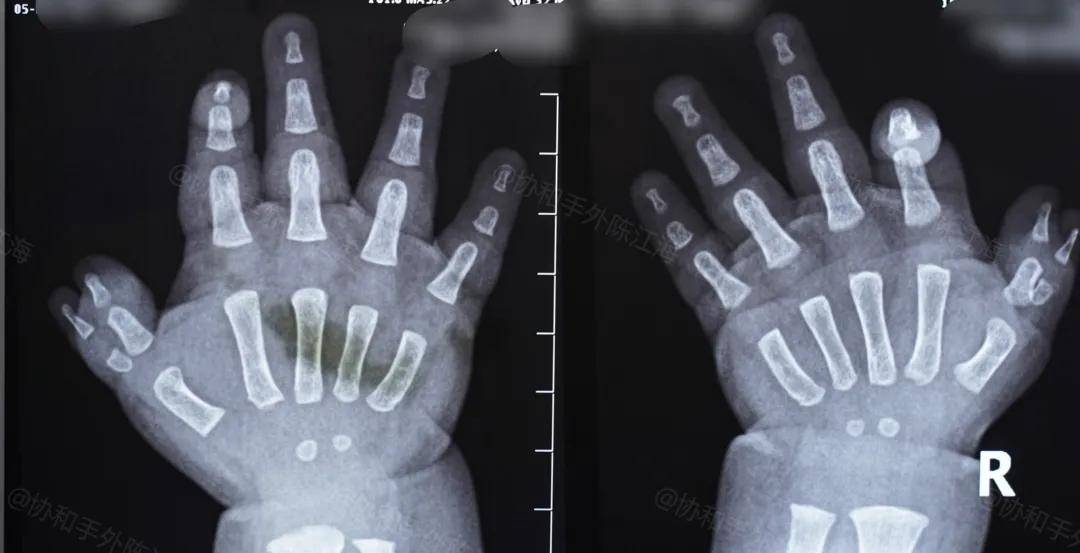

宝宝右手的多指的确有些复杂,手术不仅是去掉外侧骨头不好的小多指,还要再进行矫正,之后再通过克氏针来固定。